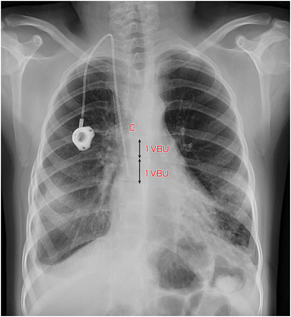

Although rarely life‐threatening, SVCS symptoms are distressing for the patient and it substantially complicates upper body vascular access, particularly if future organ transplantation or chronic renal replacement therapy is needed.5,9,10,11 Using oral instead of intravenous antibiotics with similar efficacy or use of leadless pacemakers without transvenous leads will reduce SVCS.5,9 If central venous access is required, it is important to use a catheter with the smallest diameter possible, for the shortest time, with the shortest intravenous course, and with careful catheter tip positioning.5,9,12 The superior cavoatrial junction is a safe catheter tip location, reproducibly identified on chest x‐ray as a point two vertebral body units below the carina (Box 3), where one vertebral body unit is one vertebral body and the superior adjacent vertebral disc.4,5 This is more inferior than commonly appreciated when looking at the superior aspect of the right heart border or right main bronchus on chest x‐ray.4

Box 3 – Chest x‐ray following new right internal jugular vein totally implantable venous access device (TIVAD) insertion through new stent graft with resolution of bilateral pleural effusions*

* Note the position of the catheter tip relative to the carina (C). One vertebral body unit (VBU = 1 vertebral body + 1 adjacent disc) is illustrated.